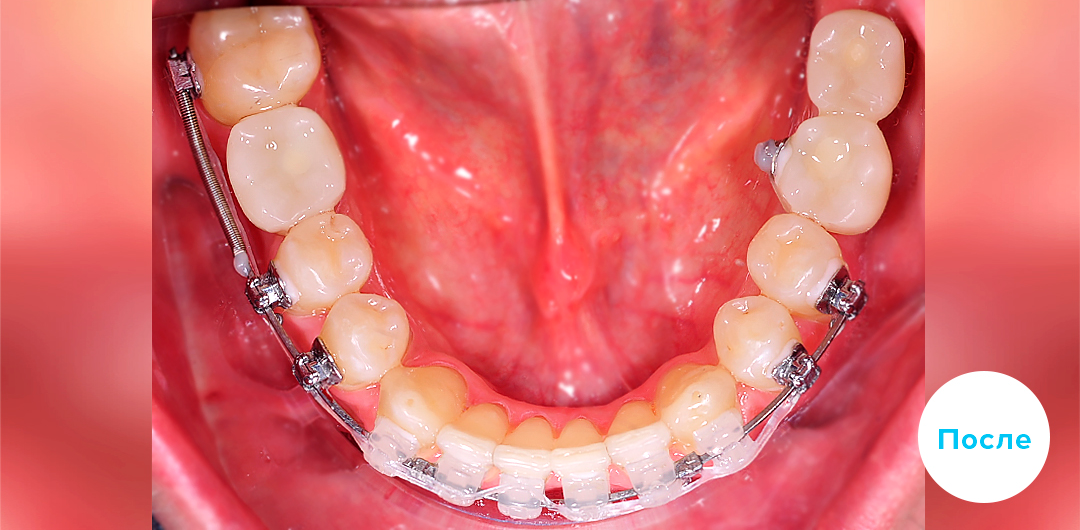

Результаты лечения